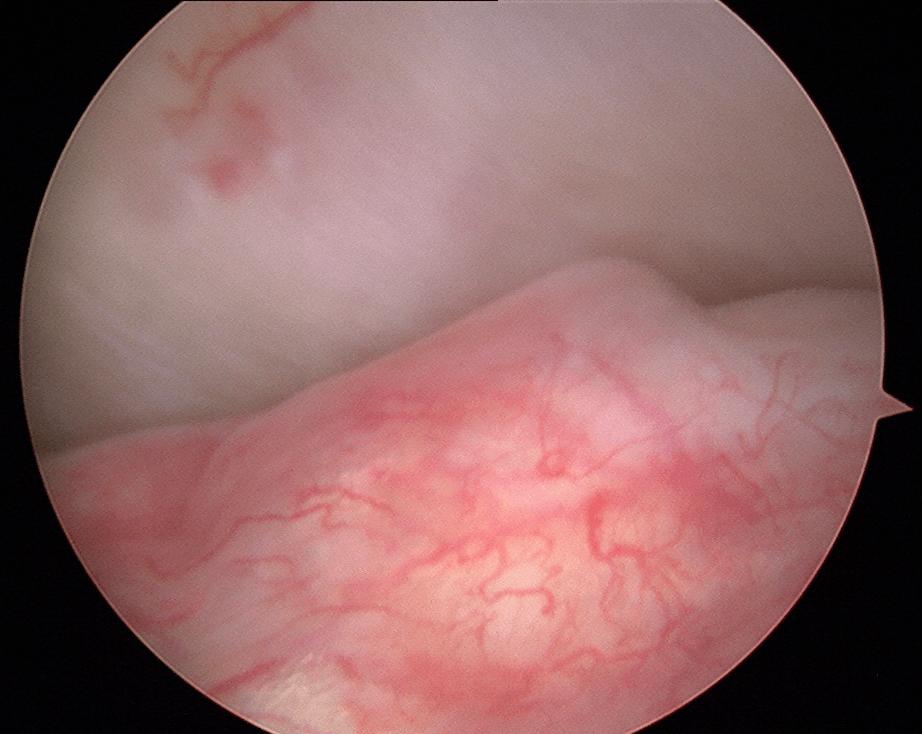

Certains DTM par contre nécessiteront une approche chirurgicale en raison de leur nature ou de l’impact significatif qu’ils ont sur la fonction. En règle générale, le chirurgien tend à choisir l’approche minimalement invasive qui est la plus appropriée dans les circonstances. Cela peut impliquer une simple infiltration articulaire, une chirurgie sous caméra (arthroscopie; approche qui permet d’avoir accès et manipuler le contenu articulaire sans avoir à ouvrir) ou dans certains cas une chirurgie ouverte (arthrotomie). Les Drs Poirier et Badri détiennent notamment des expertises dans ces champs de pratiques de par leur expérience et leur surspécialisation.

Chirurgie sous arthroscopie